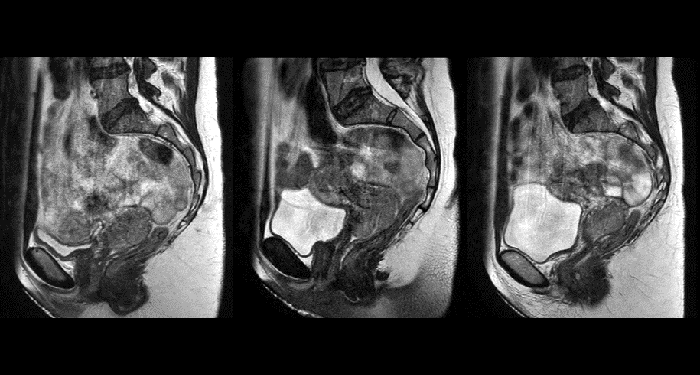

With its exceptional soft-tissue visualization capabilities and wide range of image contrasts, MRI has become a powerful tool to help more precisely define tumor boundaries. This is particularly important as it has been established that there is a high degree of uncertainty in target volume delineation, and it is even reported to represent the largest uncertainty in the entire radiotherapy process for most tumor sites**. Better visualization of the target area and nearby organs-at-risk is a key factor in enhancing target volume delineation. MRI’s expanding role also can be attributed to its functional imaging capabilities, which can inform both target characterization and treatment response.

With its superior soft tissue contrast compared to CT, MRI offers exquisite visualization of tumor boundaries and proximity to nearby critical structures.

The ability to tune contrasts can provide even more valuable information about tumor characteristics and tumor extent to facilitate enhanced delineation, and also provides possibilities for dose boosting strategies.